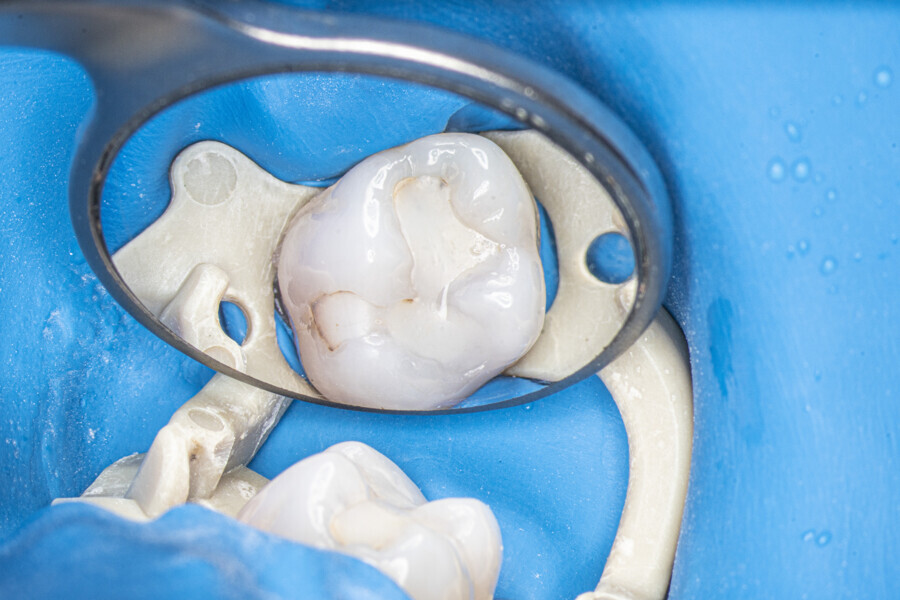

At the first appointment, both teeth were opened, the old restorations were removed, all the root canal orifices were located and the first mesiobuccal (MB1), distobuccal (DB) and palatal canals were shaped. In both teeth, the MB2 orifices were located, but the canals were not shaped. The preparation phase was similar to that explained earlier. During the root canal preparation phase, the hand file was used to establish patency after each reciprocating instrument, and the canals were flushed with NaClO activated with the SkyPulse laser in SWEEPS mode for 10–15 seconds. After reaching two-thirds of the estimated working length with the reciprocating files, the LPE enhanced irrigation protocol with the SkyPulse laser was employed. The apical preparation was not performed at this stage. Owing to a lack of time at this appointment, the canals were flushed with EDTA and sterile water, and a 2% solution of chlorhexidine was poured as an intra-canal dressing. Both teeth were closed with temporary composite restorations.

At the second appointment, the temporary restorations were removed, and the chlorhexidine was washed out with sterile water and EDTA. After opening the orifice of the MB2 canal in the first molar, the operator was not able to reach patency in the canal. Therefore, the isthmus between the MB1 and MB2 orifices was opened with diamond-coated ultrasonic tips. Finally, patency was reached. Shaping the MB2 canal in the second molar was possible only to the place of the junction with the MB1 canal. The CBCT imaging had revealed previously that the MB2 canal should have its own lumen in the apical third, but the place of the junction was below the curvature. The possibility of locating this space without damaging the root was very poor. At this stage, the LPE enhanced irrigation protocol was performed again. After performing of the irrigation protocol, the apical preparation was performed for all the canals. The final irrigation protocol was performed with 5 minutes of constant flow of 5.25% NaClO for 2 minutes, alternating with 17% EDTA for 30 seconds, with 5.25% NaClO for 30 seconds and 17% EDTA for 30 seconds, and irrigation with 5.25% NaClO for 5 minutes. All the irrigants were activated with an EDDY sonic tip (VDW). After performing the periapical radiographs, a CBCT scan was performed to confirm the separate path of the sealer that filled previously unprepared spaces of the MB2 canals in both teeth. In both cases, it was clearly visible on the CBCT image that all the previously unprepared spaces were filled with the obturation material.

A 25-year-old female patient presented to the office owing to constant pain related to the mandibular left first molar. Pulp necrosis was diagnosed. After the emergency appointment, the patient was referred for complete treatment. The tooth was treated in the same manner as described in the previous paragraphs. After creation of the access cavity, the orifices were located. In the root chamber, the orifices of the MB, mesiolingual, DB, distomesial and distolingual canals were present. After pre-flaring and preparation of the middle third, the LPE enhanced irrigation protocol with the SkyPulse laser was performed. After the irrigation protocol in the mesial root, the irrigants started to flow between lingual and buccal canals. Such an observation suggested to the operator that some space in the isthmus had been created. It is worth mentioning that at this stage apical enlargement was not performed. Final preparation of all five canals was performed with the reciprocating file, and the final irrigation protocol was performed as in the previous case. The radiograph clearly revealed that the isthmus space was filled with the sealer. The radiograph and CBCT image revealed that there were four portals of exit in the mesial root.

A 30-year-old female patient presented to the office owing to pain related to the maxillary right first molar. The radiograph revealed a periapical radiolucency, indicating exacerbated chronic periapical periodontitis. The access cavity was created with the Safe Access and Preparation Concept burs set (manufacturer). The pulp chamber was cleaned with 5.25% NaClO activated with the SkyPulse laser. Four orifices were located, and all four canals were shaped in the same sequence described previously. The LPE enhanced irrigation was performed with activation by the SkyPulse laser. In the mesial root, a clean isthmus was visible, and the irrigants started to flow between the MB1 and MB2 canals in the apical third, which was confirmed with a micro-suction cannula. In the MB1, MB2 and DB canals, apical preparation was performed with Endostar E3 Azure files (Poldent) up to size 25/0.04 owing to the apical curvatures. In the DB canal, patency was not established. The final irrigation protocol was performed in the same sequence as described before. The periapical radiograph confirmed that the isthmus was filled with the sealer.

A 35-year-old female patient was referred to the office owing to the lack of patency in the pulp chamber. The periapical radiograph and CBCT image confirmed that the pulp chamber was completely calcified. The calcification of the pulp chamber was removed with diamond-coated ultrasonic tips. After removing the calcification, four orifices were located and shaped in the sequence described previously. The LPE enhanced irrigation protocol with the SkyPulse laser was performed. In this case, the MB2 canal joined the MB1 canal approximately 4 mm before the apex and was shaped only to this length. Apical preparation and irrigation were performed as described previously. The periapical radiograph revealed that the MB2 canal had a separate apical part, which was cleaned with the irrigants and filled with the sealer, and that the palatal canal had two portals of exit.